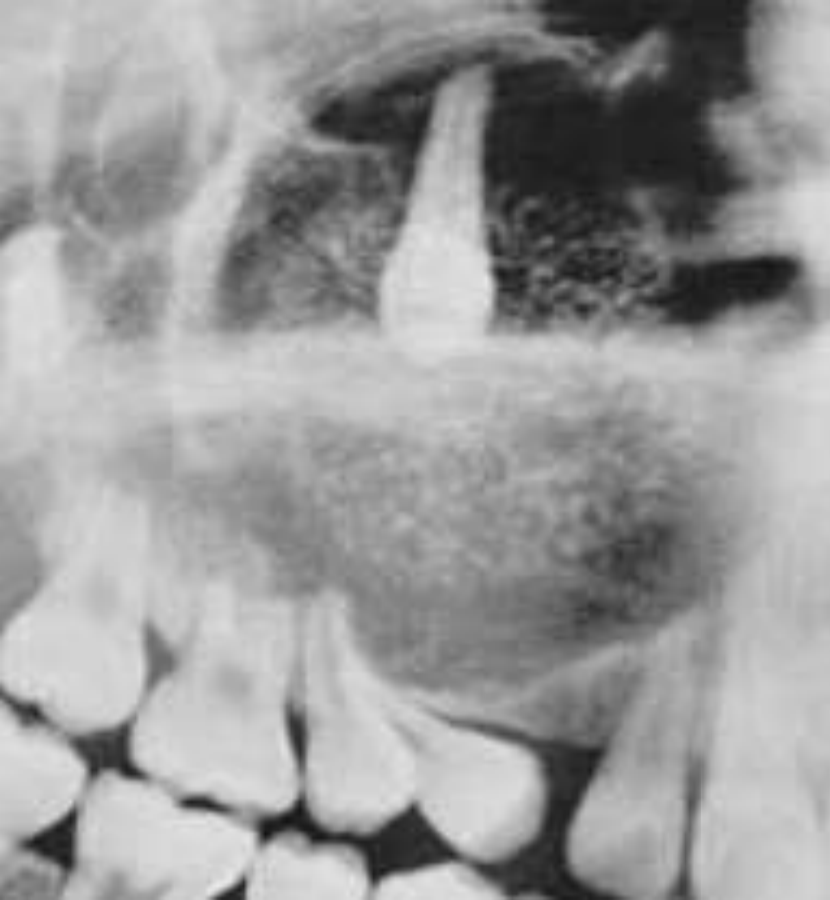

Adenomatoid Odontogenic Tumor

Well defined, corticated

Mixed density (predominantly radiolucent with some radiopacity within)

Associated with impacted maxillary lateral incisor

Displacement of adjacent teeth